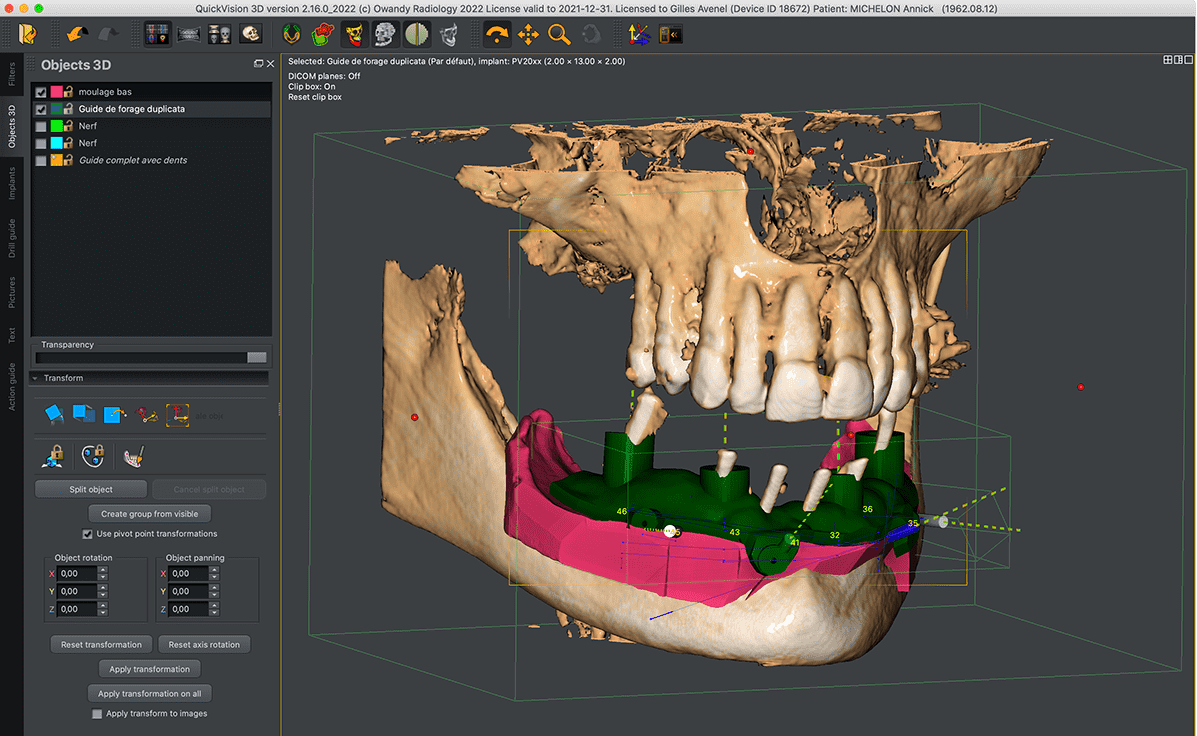

En la Clínica Mompell & Micó, sabemos que el primer paso para ofrecerte el mejor tratamiento es un diagnóstico completo y preciso. Con tecnología avanzada y un equipo especializado, aseguramos que cada detalle sea considerado para ofrecerte el mejor plan de tratamiento personalizado.